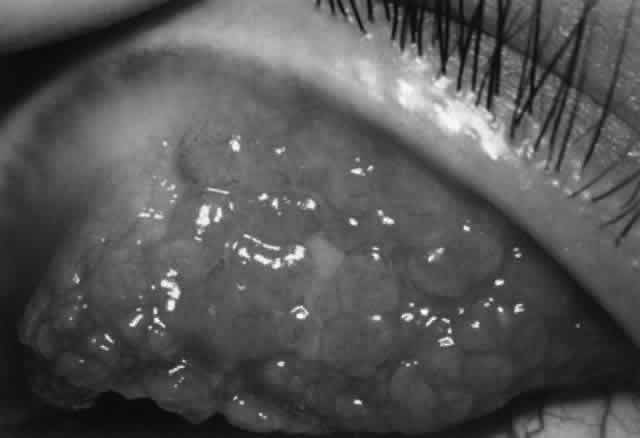

Pathogenesis

Several factors may be involved in pathogenesis. Mechanical irritation by the contact lens probably plays a role, especially lenses with thick edges, as seen in myopes. Accumulated deposits of protein, lipid, and minerals on the contact lens surface act as a source of antigens that can sensitize the conjunctiva. Chronic microtrauma by the lens and its deposits disrupts tight junctions between conjunctival epithelial cells, allowing allergens to penetrate. Damage to conjunctival epithelial cells induced by contact lenses and their deposits stimulates the production of neutrophil chemotactic factors, which play a role in the inflammatory response.83–85 Certain lens polymers (e.g., hydrogels) are more prone to accumulation of deposits. Also, larger lenses provide a greater surface area for deposits to accumulate and a greater surface area for antigens to contact the conjunctiva. Long wearing times allow a longer period of conjunctival exposure to antigen. Meibomian gland dysfunction may play a role in deposit formation and contact lens intolerance.86–88

The allergic mechanism in GPC is probably a basophil-rich delayed hypersensitivity (type IV) reaction with a possible IgE (type I) humoral component.82,89 An abnormal distribution of inflammatory cells is seen. There are mast cells in the conjunctival epithelium (not seen in normals) and increased numbers of mast cells in the substantia propria. Basophils and/or eosinophils, not usually seen in normal conjunctiva, may be found in increased numbers in both the epithelium and substantia propria.82 Although tear histamine levels are normal, tear immunoglobulins are increased.90,91 As with vernal, eosinophil major basic protein, which stimulates mast cell degranulation and possesses cytotoxic effects that may enhance the conjunctival inflammatory reaction, is found in increased amounts in the conjunctiva (but not in tears as in vernal) and undoubtedly plays a role.64 Tear tryptase levels in patients with GPC, a measure of mast cell degranulation, may provide an early marker for this disease.92

Treatment